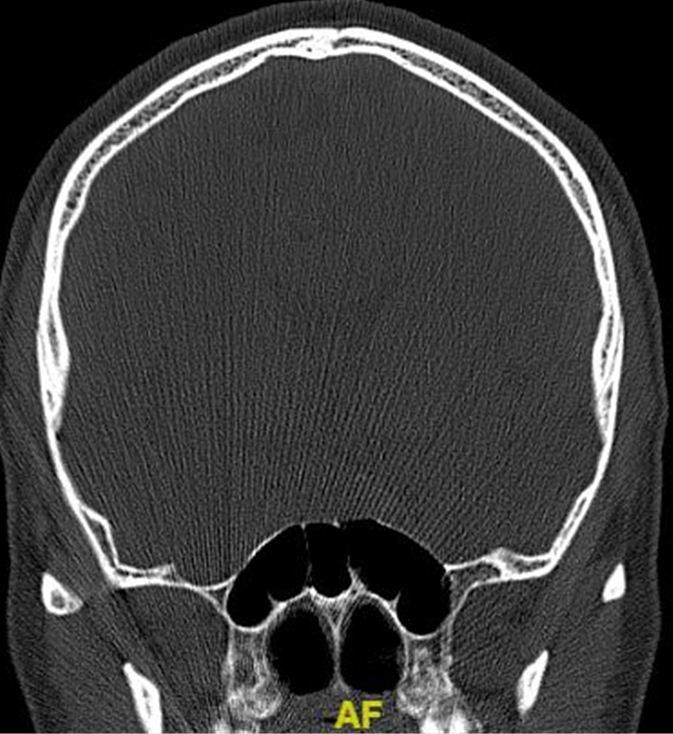

术前冠状位CT示: